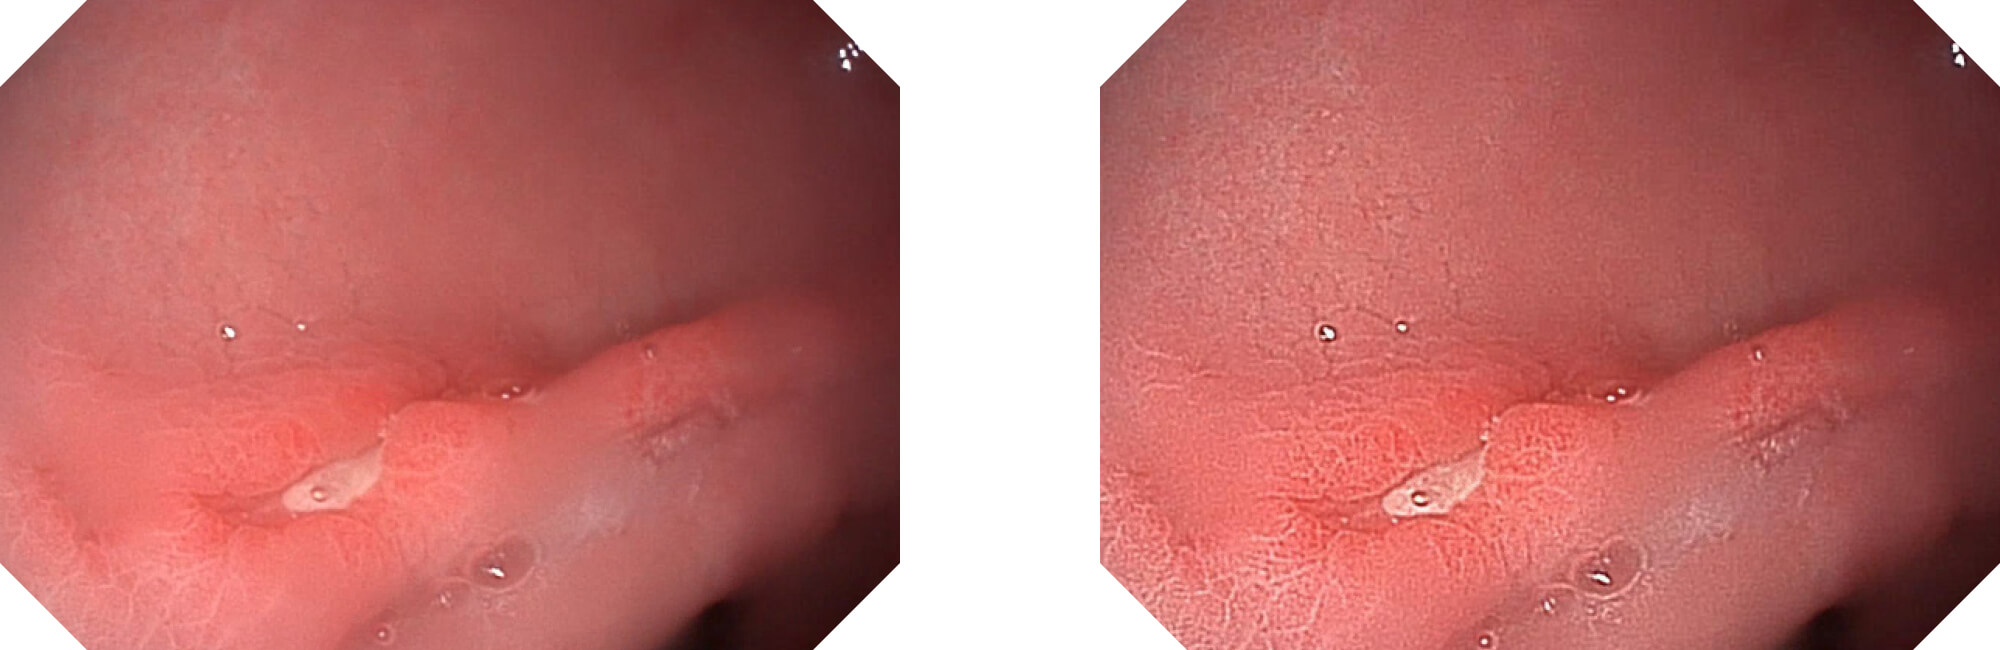

(Versatile Intelligent Staining Technology)

利用了血红蛋白在不同波长吸收下系数不同的原理,设计的一种光学域滤波和数字域滤波结合的染色技术,既保证了图像亮度,又可增强黏膜血管的对比度,充分凸显早期病变的细微结构变化,为临床疾病的观察诊断提供更丰富的参考信息。